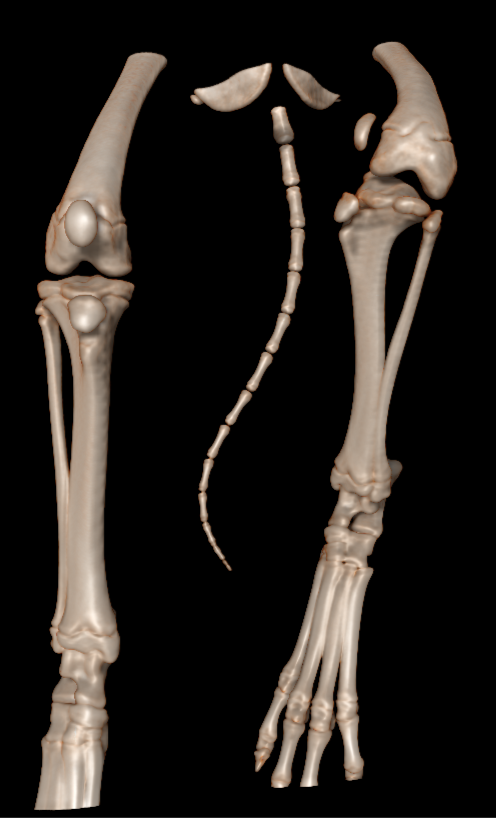

keeshond van 5 maanden met een  ernstige patella luxatie . De knieschijf zit permanent aan de binnenzijde van de knie. Het onderbeen heeft een torsie van 58.1 graden ten opzichte van het bovenbeen. Het bovenbeen heeft een kanteling van 29 graden ten opzichte van het kniegewricht.

De scan beelden zijn gebruikt om een operatieve ingreep voor te bereiden.